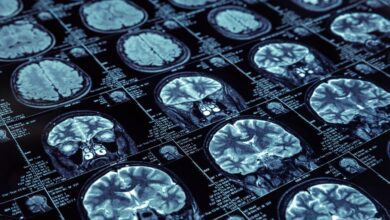

New Insights on Alzheimer’s Treatment Risks and Benefits

Recent discussions at the AD/PD annual meeting in Copenhagen have shed light on the complex relationship between the APOE ɛ4…